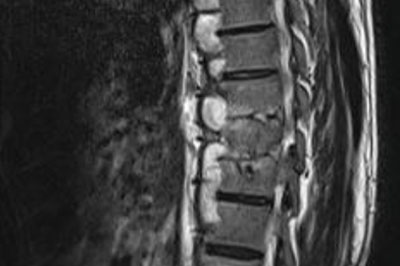

Spondylodiscitis

Infection occuring in the disc space is called as spondylodiscitis. Most commonly the infection is due to tuberculosis and rerely by other bacterias and fungus...

• Spinal infections - tuberculous and pyogenic infections